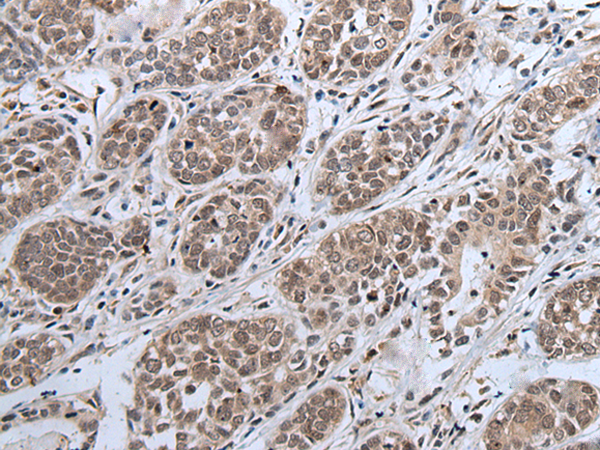

IHC positive control: |

Human esophagus cancer and human tonsil |